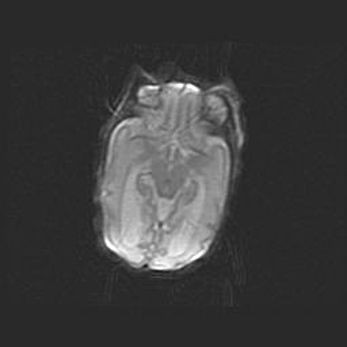

Неполная лизэнцефалия (пахигирия). Открытая гидроцефалия.

Возраст: 17 дней

Вес: 3110 г

Пол: мужской

Окружность головы: 33,5 см

Срок гестации: 35-36 недель

Лизэнцефалия—недоразвитие корковой пластинки и мозговых извилин в результате нарушения миграции нейронов коры. Поверхность мозговых полушарий гладкая. Микроскопически выявляется отсутствие нормальных слоев коры и скопление групп нейронов в подкорковом белом веществе.

Пахигирия—уменьшение числа вторичных извилин. В пораженном полушарии нервные клетки образуют толстый недифференцированный слой с неправильно расположенными нервными волокнами и группами гетеротопных клеток. Нервные клетки незрелые. Белое вещество истончено. При этом нередко аномально развит корково-спинномозговой путь.